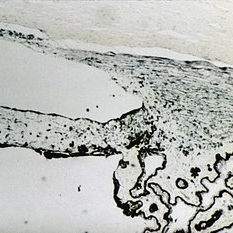

Slide 7-64

Feb 25 2019 by Lancaster Course in Ophthalmology

Rupture of Descemet's membrane with a gap in the posterior stroma.

Condition/keywords: descemet's membrane, rupture, stroma